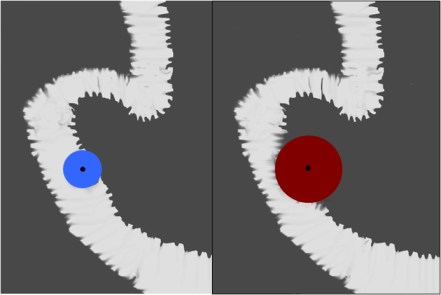

SIGNO DEL SANDWICH

Signo de linfoma abdominal tanto en la TC como en ecografía. Consiste en la presencia de masas adenopáticas que rodean y desplazan la arteria y la vena mesentéricas superiores sin comprimirlas.

La fotografía corresponde a un paciente con linfoma (flecha roja) que forma conglomerados adenopáticos que respetan los vasos mesentéricos (flecha blanca).

Por extensión, se puede emplear este signo en conglomerados linfomatosos que rodean pero respetan otras estructuras vasculares diferentes de los vasos mesentéricos, como vemos en el ejemplo siguiente con las arterias renales.